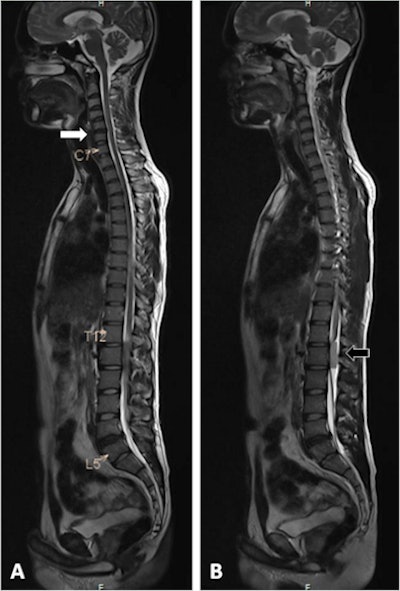

This 42-year-old male patient presented with axial neck pain and right upper-limb radiculopathy. Whole-spine T2-weighted sagittal screening images (a, b) show mild disk bulge at C5-6 (white arrow), and an intradural extramedullary tumor behind the body of L1 vertebra (black arrow). Image courtesy of Dr. Rishi Kanna and European Spine Journal.The group aimed to show how detailed images of the spinal column and adjacent spinal regions and paravertebral organ systems can reveal asymptomatic yet significant incidental findings.